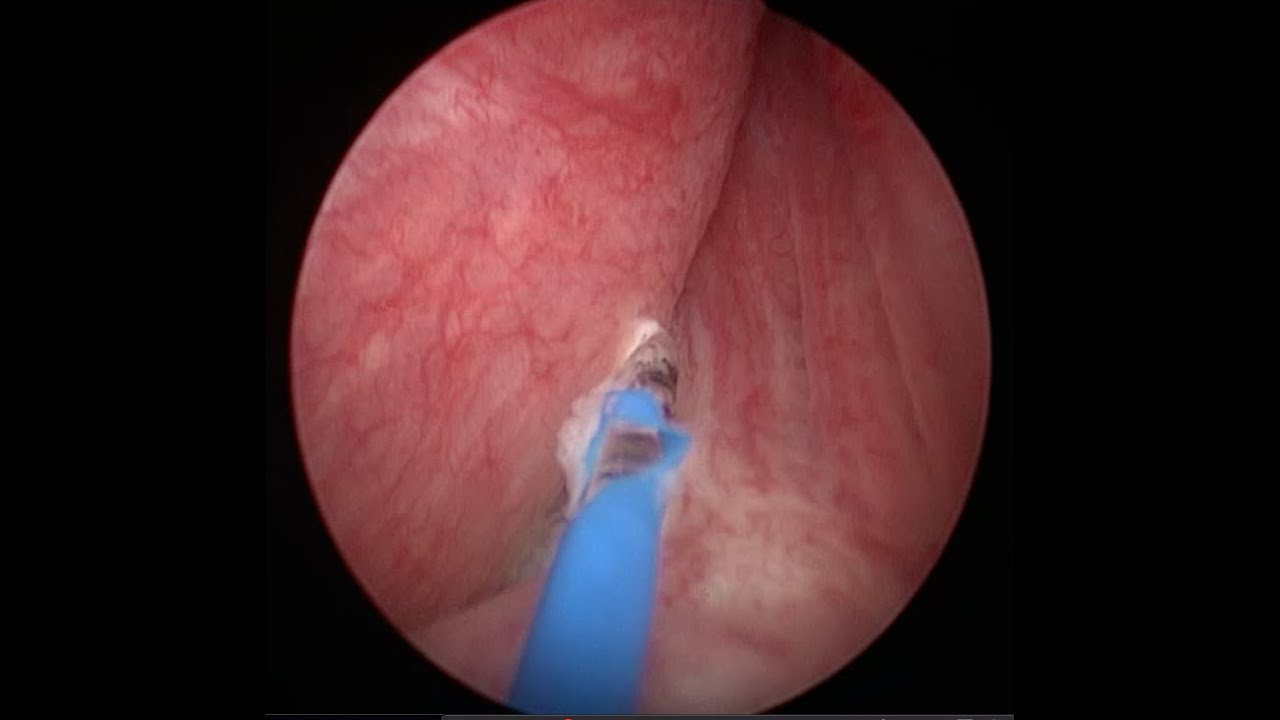

Mi nombre es Miguel Ángel Rodríguez Cabello. Soy médico licenciado por la Universidad de Alcalá y especialista en Urología formado en el Hospital Universitario Ramón y Cajal. Terminé mi formación como especialista en Urología en el año 2015 de la mano de grandes profesionales y maestros, y trato de transmitir todos mi conocimientos y habilidades para el beneficio de mis pacientes. También he completado mi etapa universitaria con el Doctorado, que defendí en la Universidad Autónoma de Madrid en junio de 2023 con resultado Cum Laude. He recibido formación en cirugía robótica (INTUITIVE - DaVinci Xi y SP) en Saint Augustin Clinic de (Burdeos) y estoy acreditado para su utilización por la agencia IRCAD (Strasbourg, France) desde 2017. Tengo amplia experiencia en el manejo de la hiperplasia de próstata con técnicas como la enucleación y vaporización con láser y con la moderna técnica robótica denominada hidroablación - AQUABEAM -, Por último, mi campo de trabajo e investigación más puntera es el diagnóstico y tratamiento del cáncer de próstata (biopsia fusión, terapia focal, prostatectomía radical...), temática que abarca gran parte de mi actividad profesional.

Diagnóstico y tratamiento de la hiperplasia de próstata (HBP) mediante láser, REZÜM y AQUABEAM.

Biopsia de próstata por fusión. Cirugía robótica (DaVinci, AQUABEAM). Cirugía de la hiperplasia de próstata con láser, REZÜM y Aquabeam. Terapia focal en cáncer de próstata (crioterapia, HIFU). Vasectomía sin bisturí. Circuncisión sin bisturí (CIRCURER). Segundas opiniones médicas. Ensayos clínicos en infecciones del tracto urinario.

Siguiendo sus consejos me sometí primero a una operación para extraer dichas piedras y al mes me realice la operación para la hiperplasia mediante la técnica AQUABEAM.

El sistema AQUABEAM, comparando con otros amigos que pasaron por la técnica del laser, me han permitido un postoperatorio cómodo e indoloro.